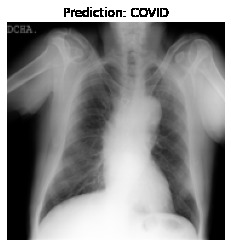

Currently, there is an urgent need for efficient tools to assess the diagnosis of COVID-19 patients. In this project, we propose a constructive solution for detecting and labeling infected tissues on CT lung images of such patients. To cut down false positives our model is trained on 4 types of lung CT images : COVID, Viral Pneumonia, Lung Opacity and normal images to get the best possible results with highest accuracy.

We built it using Tensorflow 2.x using Python. We have developed a Convolutional Neural Network model with an average accuracy of more than 85%.

We learned that COVID-19 can be succesfully detected through LUNG-CT images instead of tedious tests like Reverse transcription polymerase chain reaction (RT-PCR) which takes almost 5 hours and Rapid detection tests which has a low accuracy.

Our model contains the best of both worlds with quick detection and high accuracy.